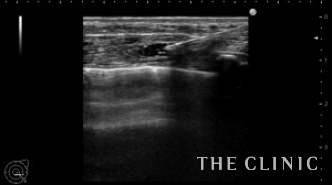

比較のためヒアルロン酸が入っていない部位をまずはご覧ください。

こちらは大胸筋内に細かくヒアルロン酸が注入されています。